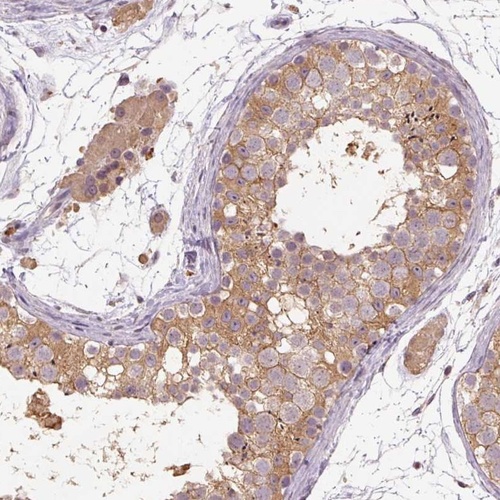

Immunohistochemical staining of human testis shows moderate cytoplasmic positivity in cells in seminiferous ducts and Leydig cells.